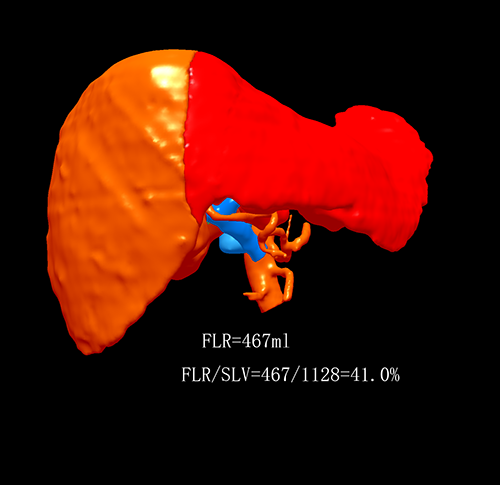

右肝肿瘤---右半肝切除